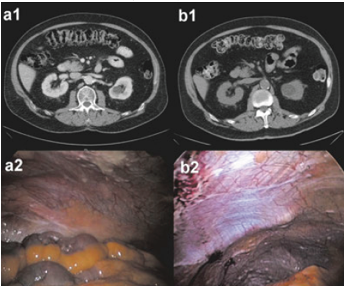

Peritoneal carcinomatosis (diffuse cancer in the abdomen) is difficult to diagnose. Imaging techniques such as computed tomography and MRI can help plan surgical intervention. However, since these examinations have low sensitivity in the diagnosis of small-volume disease, they may be insufficient in the detection of localized peritoneal carcinomatosis. Therefore, direct visualization of the peritoneum (peritoneum) by laparoscopy or laparotomy is the "Gold Standard" in the diagnosis of peritoneal carcinomatosis.

1.Computed Tomography (CT Scan): Contrast-enhanced computed tomography is the standard imaging modality for the diagnosis of peritoneal carcinomatosis (peritoneal cancer invasion), although its accuracy in detecting small peritoneal involvement remains limited. However, there is a 30-45% risk of missed lesions smaller than 5 mm.

5.Diagnostic Laparoscopy: Preoperative assessment of the extent of peritoneal carcinomatosis is difficult; a clear assessment is often made during surgical exploration. Staging with conventional imaging methods can often be limited, leading to incorrect staging or unnecessary laparotomy (opening the abdomen through incision). Diagnostic laparoscopy can provide detailed information about intra-abdominal cancer and histologic confirmation of suspected peritoneal carcinomatosis. It can also be used effectively to evaluate the effects of neoadjuvant (preoperative) chemotherapy.